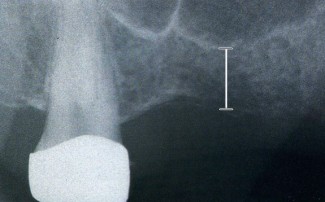

Questa tecnica chirurgica viene eseguita per ottenere un aumento volumetrico in altezza di poche millimetri (2-3 mm), in un sito con spessore osseo insufficiente in altezza (6-8 mm).

Questa tecnica viene eseguita qualora esista un ridottissimo volume di osso residuo in altezza nelle zone posteriori della mascella per poter posizionare degli impianti

In questa situazione occorre un aumento del volume osseo verticale mediante il grande rialzo del seno mascellare. Da un accesso operatorio intraorale il pavimento del seno è esposto e la membrana di rivestimento del seno è sollevata delicatamente.

Lo spazio formatosi viene riempito di osso autologo particolato e/o osso artificiale.

In presenza di uno spessore sufficiente di osso basale residuo (circa 4-5mm) gli impianti possono essere inseriti contemporaneamente al rialzo del seno mascellare. Altrimenti si rigenera dchirima l'osso e si procede al posizionamento degli impianti solo dopo un tempo di attesa di 6-8 mesi.